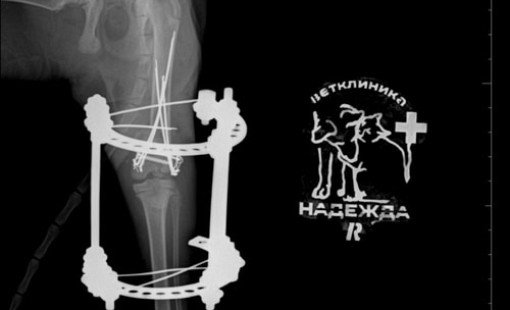

Случаи из практики

Ветеринарная клиника Надежда

За более чем 30-ти летнюю практику наши ветеринары сталкивались в различными случаями болезней и травм животных. Это дало нам огромный опыт в лечении и реабилитации. Мы беремся даже за самые сложные случаи! С любовью и заботой относимся к животным, стараемся сделать так, чтобы они испытывали минимум дискомфорта во время лечения и реабилитации.